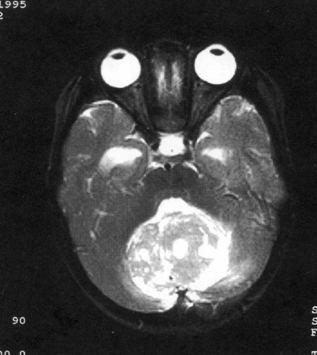

病历摘要:??患儿男性,11岁。半年前开始出现行走不稳,常无故跌倒。半月前出现发作性剧烈头痛,伴恶心呕吐。体检:T36℃,P100次/分,R22次/分,B...

问题 病历摘要:??患儿男性,11岁。半年前开始出现行走不稳,常无故跌倒。半月前出现发作性剧烈头痛,伴恶心呕吐。体检:T36℃,P100次/分,R22次/分,BP100/60mmHg,神清,言语较缓慢,双眼外展约不及边,双眼侧视时有小幅度水平眼震。四肢肌力正常,右上肢肌张力较低,坐位姿势不稳,常不自主摇晃,双上肢指鼻不准,行走蹒跚步态,足距扩大,身前倾。 下一步应首先行何种后续治疗?提示:经腰穿置管脑脊液外引流等处理,脑脊液渗漏停止。肿瘤病理为髓母细胞瘤。